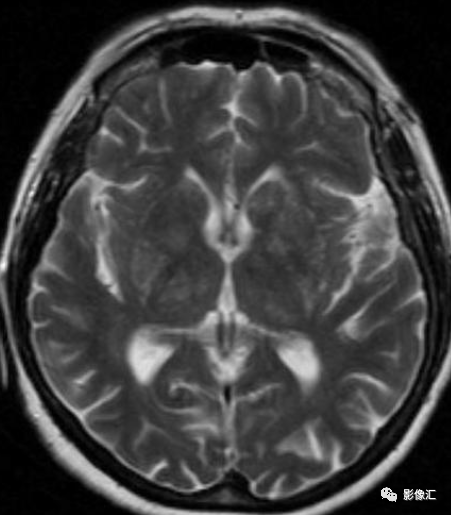

【病例欣賞】大腦也跳舞-非酮癥高血糖偏側舞蹈癥影像非酮癥高血糖偏側舞蹈癥影像60歲,女性,因左上、下肢無力及抽搐20天就診,伴有中風樣癥狀和嘔吐。糖尿病患者。影像表現(xiàn):平掃MR顯示右側豆狀核和尾狀核(基底神經節(jié))見T1高信號病灶,軸位T2和FLAIR圖像上呈稍高信號,DWI呈等、稍低信號。?非酮癥高血糖偏側舞蹈癥(HC-NH)非酮癥高血糖性偏側舞蹈癥又稱糖尿病紋狀體病或舞蹈病、高血糖、基底神經節(jié)(CH-BG)綜合征,是一種罕見的非酮癥高血糖神經系統(tǒng)并發(fā)癥,與非酮癥高滲性昏迷和非酮癥一樣高血糖發(fā)作。它是偏側舞蹈-偏側彈力綜合癥的一個原因。由Jones等于1985年首先報道,該病多見于血糖控制不良的老年糖尿病患者,可表現(xiàn)為累及單側或雙側肢體的舞蹈樣動作及面部的不自主運動。典型表現(xiàn)為三聯(lián)征:非酮癥性高血糖、偏側舞蹈癥及癥狀肢體對側紋狀體MRIT1WI高信號、CT平掃高密度。該病的發(fā)病機制尚未明確,Hsu等對3例患者行PET檢查,發(fā)現(xiàn)病變側基底節(jié)區(qū)糖代謝較對側顯著降低。一般認為NC-NH患者基底節(jié)區(qū)平時由于微血管病存在慢性缺血,但未有真正梗死發(fā)生,當高血糖發(fā)生時,局部腦血流下降及糖代謝衰竭,三羧酸循環(huán)被抑制,腦細胞以γ一氨基丁酸為能量來源,酮癥患者有乙酰乙酸作為再合成γ一氨基丁酸的物質,而非酮癥患者的γ一氨基丁酸將很快耗竭,導致基底節(jié)正?;顒邮艿綋p害,從而表現(xiàn)出癥狀?;颊唢B腦CT和MRI均顯示病灶局限于基底節(jié)區(qū),故也支持高血糖導致紋狀體細胞代謝功能紊亂從而引起發(fā)作性舞蹈徐動癥的觀點。在對HC-NH患者CT檢查中可發(fā)現(xiàn)基底節(jié)區(qū)高密度影,在MRI檢查中可發(fā)現(xiàn)基底節(jié)區(qū)T1WI,T2WI以及DWI上高信號,其中以T1WI最具特征性。大多數(shù)患者的MRI表現(xiàn)可隨著癥狀的好轉而消失,但仍有少部分的病例MRI正常后癥狀仍持續(xù)存在,其具體機制仍不明確。既往多數(shù)研究者認為與點狀出血相關,也可能有脫髓鞘改變以及鈣鹽沉積參與。但近期有人在對HC-NH的MRI隨訪以及對DWI表觀彌散系數(shù)的分析后提出可能與高黏血癥、細胞毒性水腫以及低灌注后腦缺血相關。HC-NH特征性影像學表現(xiàn)為,患側肢體對側紋狀體MRIT1像高信號、CT平掃高密度,部分病例影像學改變是可逆的,在基底節(jié)區(qū)其他結構性或代謝性損害中未見到這種影像學改變。DWI上病灶呈稍低信號,T2相呈等或稍低信號。影像學表現(xiàn)形成機制目前解釋說法不一:可逆性鈣鹽或某種未知物質沉積;膠質細胞增生;代謝紊亂引起的斑片狀出血;腦缺血等。既往學者根據(jù)患者急性起病,CT顯示基底節(jié)區(qū)高密度,CT值40~50HU,認為是斑片狀出血。但不同于常規(guī)血腫,病灶局限,信號不均勻,但不累及丘腦和內囊等周圍組織,無占位效應?;颊咭酂o明顯的頭痛、嘔吐及偏癱等臨床癥狀。其在MRI的信號改變也不符合通常血腫的時間演變規(guī)律。臨床特點:1、見于糖尿病患者;2、以急起的舞蹈樣投擲動作為特征,一般無神經系統(tǒng)其他的癥狀和體征;3、發(fā)病時血糖高,但血酮體陰性;4、CT顯示基底節(jié)區(qū)密度稍高,多為單側,也可以表現(xiàn)為雙側,MRI表現(xiàn)為短T1信號,T2像改變不明顯,也可出現(xiàn)稍短T2或者稍長T2的表現(xiàn),DWI呈低信號或正常,少部分也可以呈稍高信號,增強掃描多無強化或輕度強化;5、疾病病理不明,可能與高血糖導致局部血管通透性增加導致血管滲血有關,也可能與高血糖所致的局部代謝障礙有關;6、首先應盡快糾正高血糖,同時可予氟哌啶醇等對癥處理;7、預后:糾正高血糖后大部分病人癥狀消失。鑒別診斷:1.蒼白球的生理性鈣化顱腦CT掃描時發(fā)現(xiàn)蒼白球鈣化屬于正常的生理現(xiàn)象,通常雙側比較對稱,但也可不對稱。但如果鈣化出現(xiàn)在30歲以下,應警惕為病理性鈣化。應仔細詢問有無癲癇等相關臨床癥狀或進行有關鈣、磷代謝和內分泌方面的臨床生化檢查。2.甲狀旁腺功能減低甲狀旁腺功能減低是由甲狀旁腺素分泌減低而引起的低血鈣、手足抽搐、局灶性癲癇等,易被臨床誤診為原發(fā)性癲癇。CT表現(xiàn)主要為腦內鈣化,以基底核最常見,發(fā)生率100%,常呈兩側對稱性。蒼白球及丘腦鈣化發(fā)生率為90%,其次可見小腦齒狀核、腦葉,腦葉鈣化多見于額、頂、顳葉,85%位于灰白質交界處,亦可見于半卵圓中心,基本呈對稱分布。多數(shù)病例內囊區(qū)雖然被鈣化的尾狀核、殼核、蒼白球、丘腦包繞,但本身并不鈣化,稱為“內囊空白征”。3.特發(fā)性家族性腦血管亞鐵鈣沉著癥(Fahr?。〧ahr病為家族性特發(fā)性基底節(jié)鈣化,臨床癥狀有精神發(fā)育遲緩或癡呆、癲癇、錐體束或錐體外系受累癥狀,無鈣磷代謝異常和特殊體型,有的毫無癥狀,CT上可見基底節(jié)區(qū)對稱性鈣化,大小形狀不一,位于尾狀核、豆狀核和內囊,部分可達外囊,偶見基底節(jié)區(qū)囊性變,有的病人丘腦、下丘腦區(qū)可見類似鈣化灶。4.結節(jié)性硬化(室管膜下結節(jié))CT表現(xiàn)為室管膜下多發(fā)結節(jié)狀鈣化影,有家族史,多見于兒童,主要臨床表現(xiàn)以智能低下較明顯,面部有皮脂腺瘤及癲癇發(fā)作。